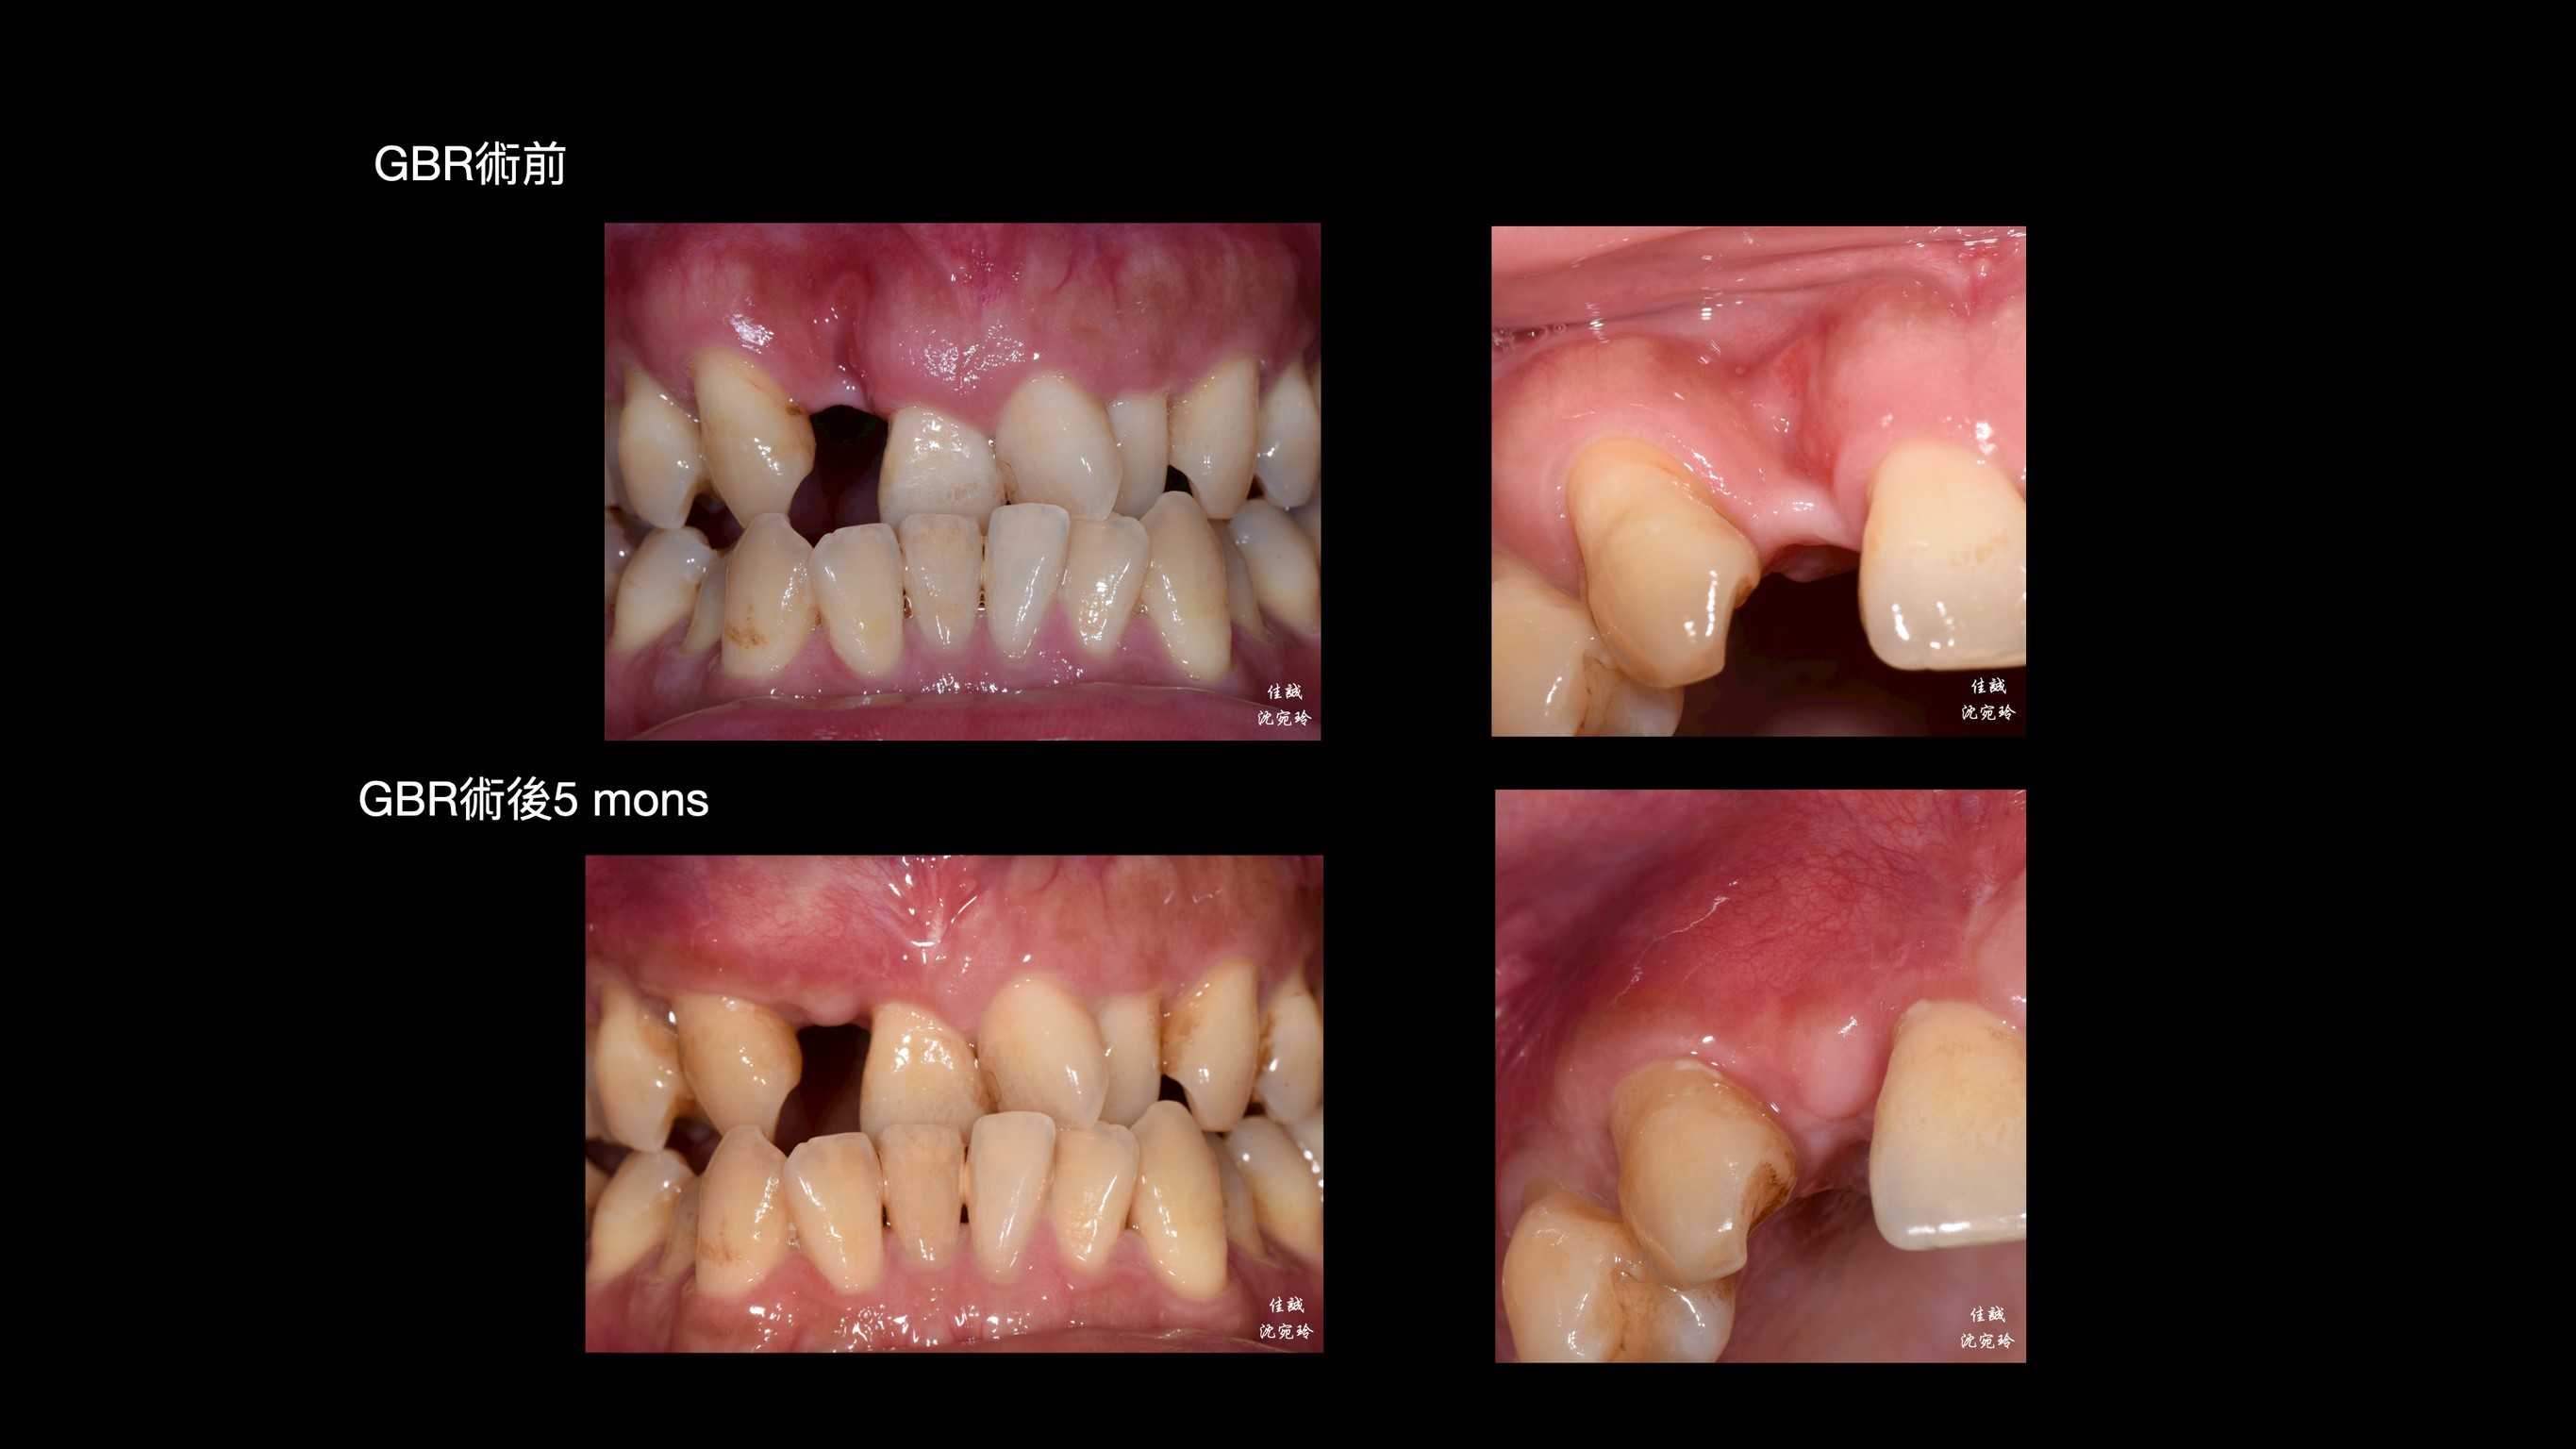

感謝醫師轉診,C先生自述右上側門牙因牙周病太搖而自行掉落,上前來「評估缺牙區可否植牙或是假牙?」

由於骨缺損程度大,此區若直接做假牙除了會塞食物,也不美觀。另外,做牙橋會犧牲太多齒質,需要根管治療;而馬里蘭牙橋做在平行度不佳的前後牙齒上面,也需要修磨較多,使用年限也不高;加上咬合排列不正,建議先做補骨手術,再接著做矯正治療,等矯正完成後,才做植牙或假牙的選擇。

手術挑戰是術區牙齦皮薄、骨缺損大,加上病患希望矯正前只開一次手術,對於方便矯正的接續進行,這次只補FDBA和 OSSIX plus。因為預期將來會吸收一些,我盡量補oversize,最後選在牙齒掉落後的三個月進場,增加贏面。

幾個月後,也仰賴病患體氣血循好,成果還不錯唷。